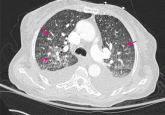

ArticleDiffuse reticulonodular infiltratesAuthor:Vicente Jose M. Velez, MD, FACPPublish date: January 1, 2012A 69-year-old woman has fever of unknown origin and dyspnea. Her past provides a clue to the diagnosis.Read More